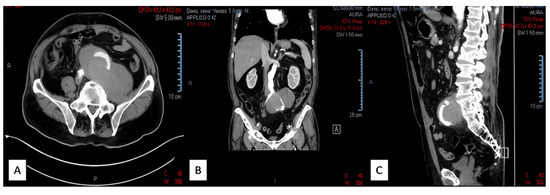

2.2. Case Report II